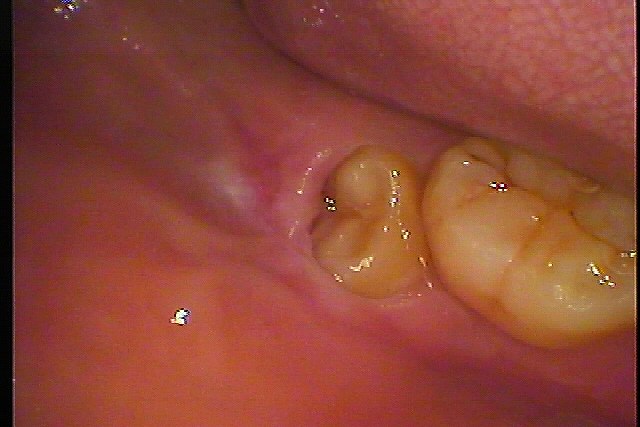

ブログ一覧|広島市安佐南区の歯科医院 ブログ一覧 トップ ブログ一覧 お知らせ スタッフブログ ブログ一覧 2017/12/06 CTデータからひも解くインプラント埋入位置。 2017/12/06 CTにより解剖学的形態を避け、安全に顎骨内にインプラントを埋入することが大切です。 2017/12/06 術後のレントゲンになります。 2017/12/06 インプラント埋入における術前、術後診査。 2017/12/06 インプラントにおけるCTデータの確認。 スタッフブログ 2017/12/05 今日はとってもいいことがありました。 頑張ってください、 応援しています。 2017/12/05 親不知の抜歯。 すぐ抜けるケースの1つかと思います。 2017/12/05 先が折れてしまいました。 除去しています。 << 1 2 3 4 5 … 808 809 810 811 812 … 870 871 872 873 874 >> Web診療予約 初めての方へ 選ばれ続ける理由 院内設備について 歯が痛いしみる一般歯科 歯がぐらぐらする歯周病 健康な歯を保ちたい予防歯科 子供の虫歯予防をしたい小児歯科 銀歯をセラミックに審美歯科 白い歯を目指しませんか?ホワイトニング 矯正専門医がいるので安心矯正歯科 抜けた歯を補いたいインプラント・入れ歯 医院案内 スタッフ紹介 メリィハウス歯科クリニックオフィシャルホームページ ラベンダー歯科クリニックオフィシャルホームページ お知らせ・ブログ ホーム 診療科目 一般歯科 歯周病治療 予防治療 小児歯科 審美治療 ホワイトニング 矯正歯科 入れ歯・インプラント マウスピース矯正 初めての方へ 院長・スタッフ 設備紹介 医院案内・アクセス メニューを閉じる